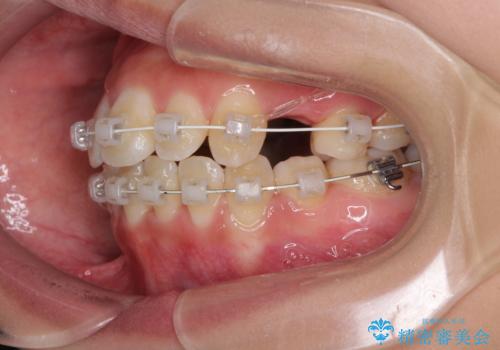

前歯の正中のズレを改善 目立たないワイヤー装置での抜歯矯正

- 矯正装置

- 審美装置

- 八重歯を気にして来院された患者様です。

上下ともに前突感と叢生が認められ、上顎の正中が著しく右側にずれていたため、上下左右第一小臼歯4本を抜歯し、ワイヤー矯正にて治療を行うこととしました。

移動量が多かったため、治療期間は通常より半年~1年ほど長くかかりましたが、上下の正中をほぼ同じ位置にまで移動させることができました。